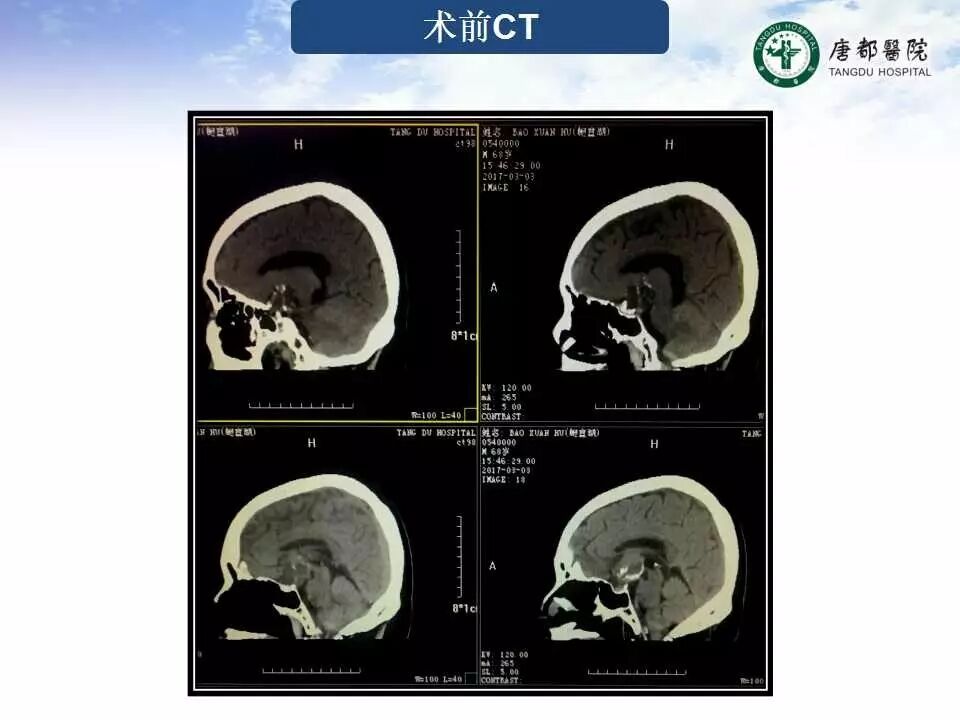

Case 2